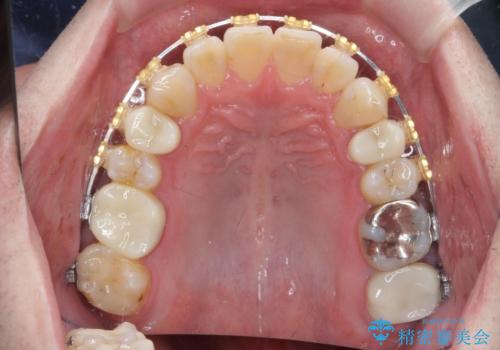

- 矯正装置

- ワイヤー矯正

- 治療期間

- 1年6ヶ月

- 今装着されている全ての銀歯の除去、虫歯の治療、矯正治療を含めた総合治療を希望され来院されました。

放置すると大きくなりそうな虫歯をまず治療、矯正治療を行ったのち、全ての銀歯を除去しセラミック治療を行う治療計画としました。